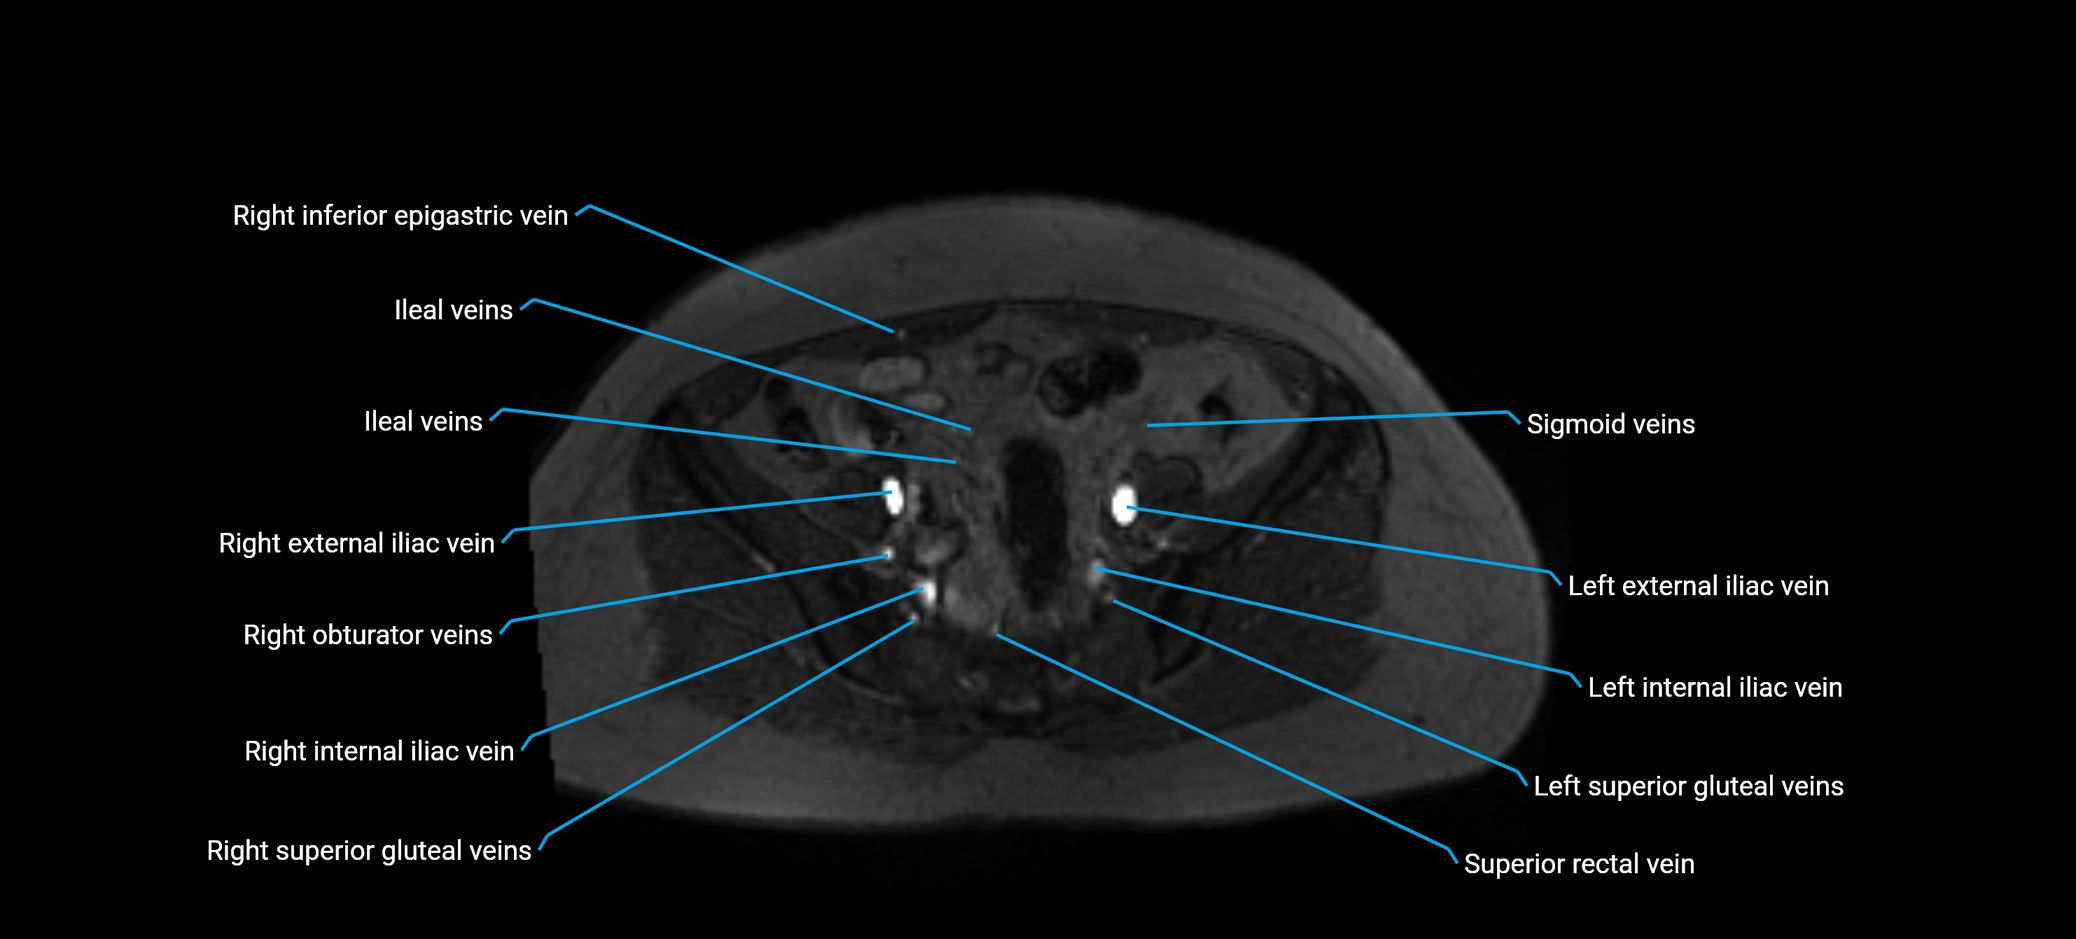

MRI image

image